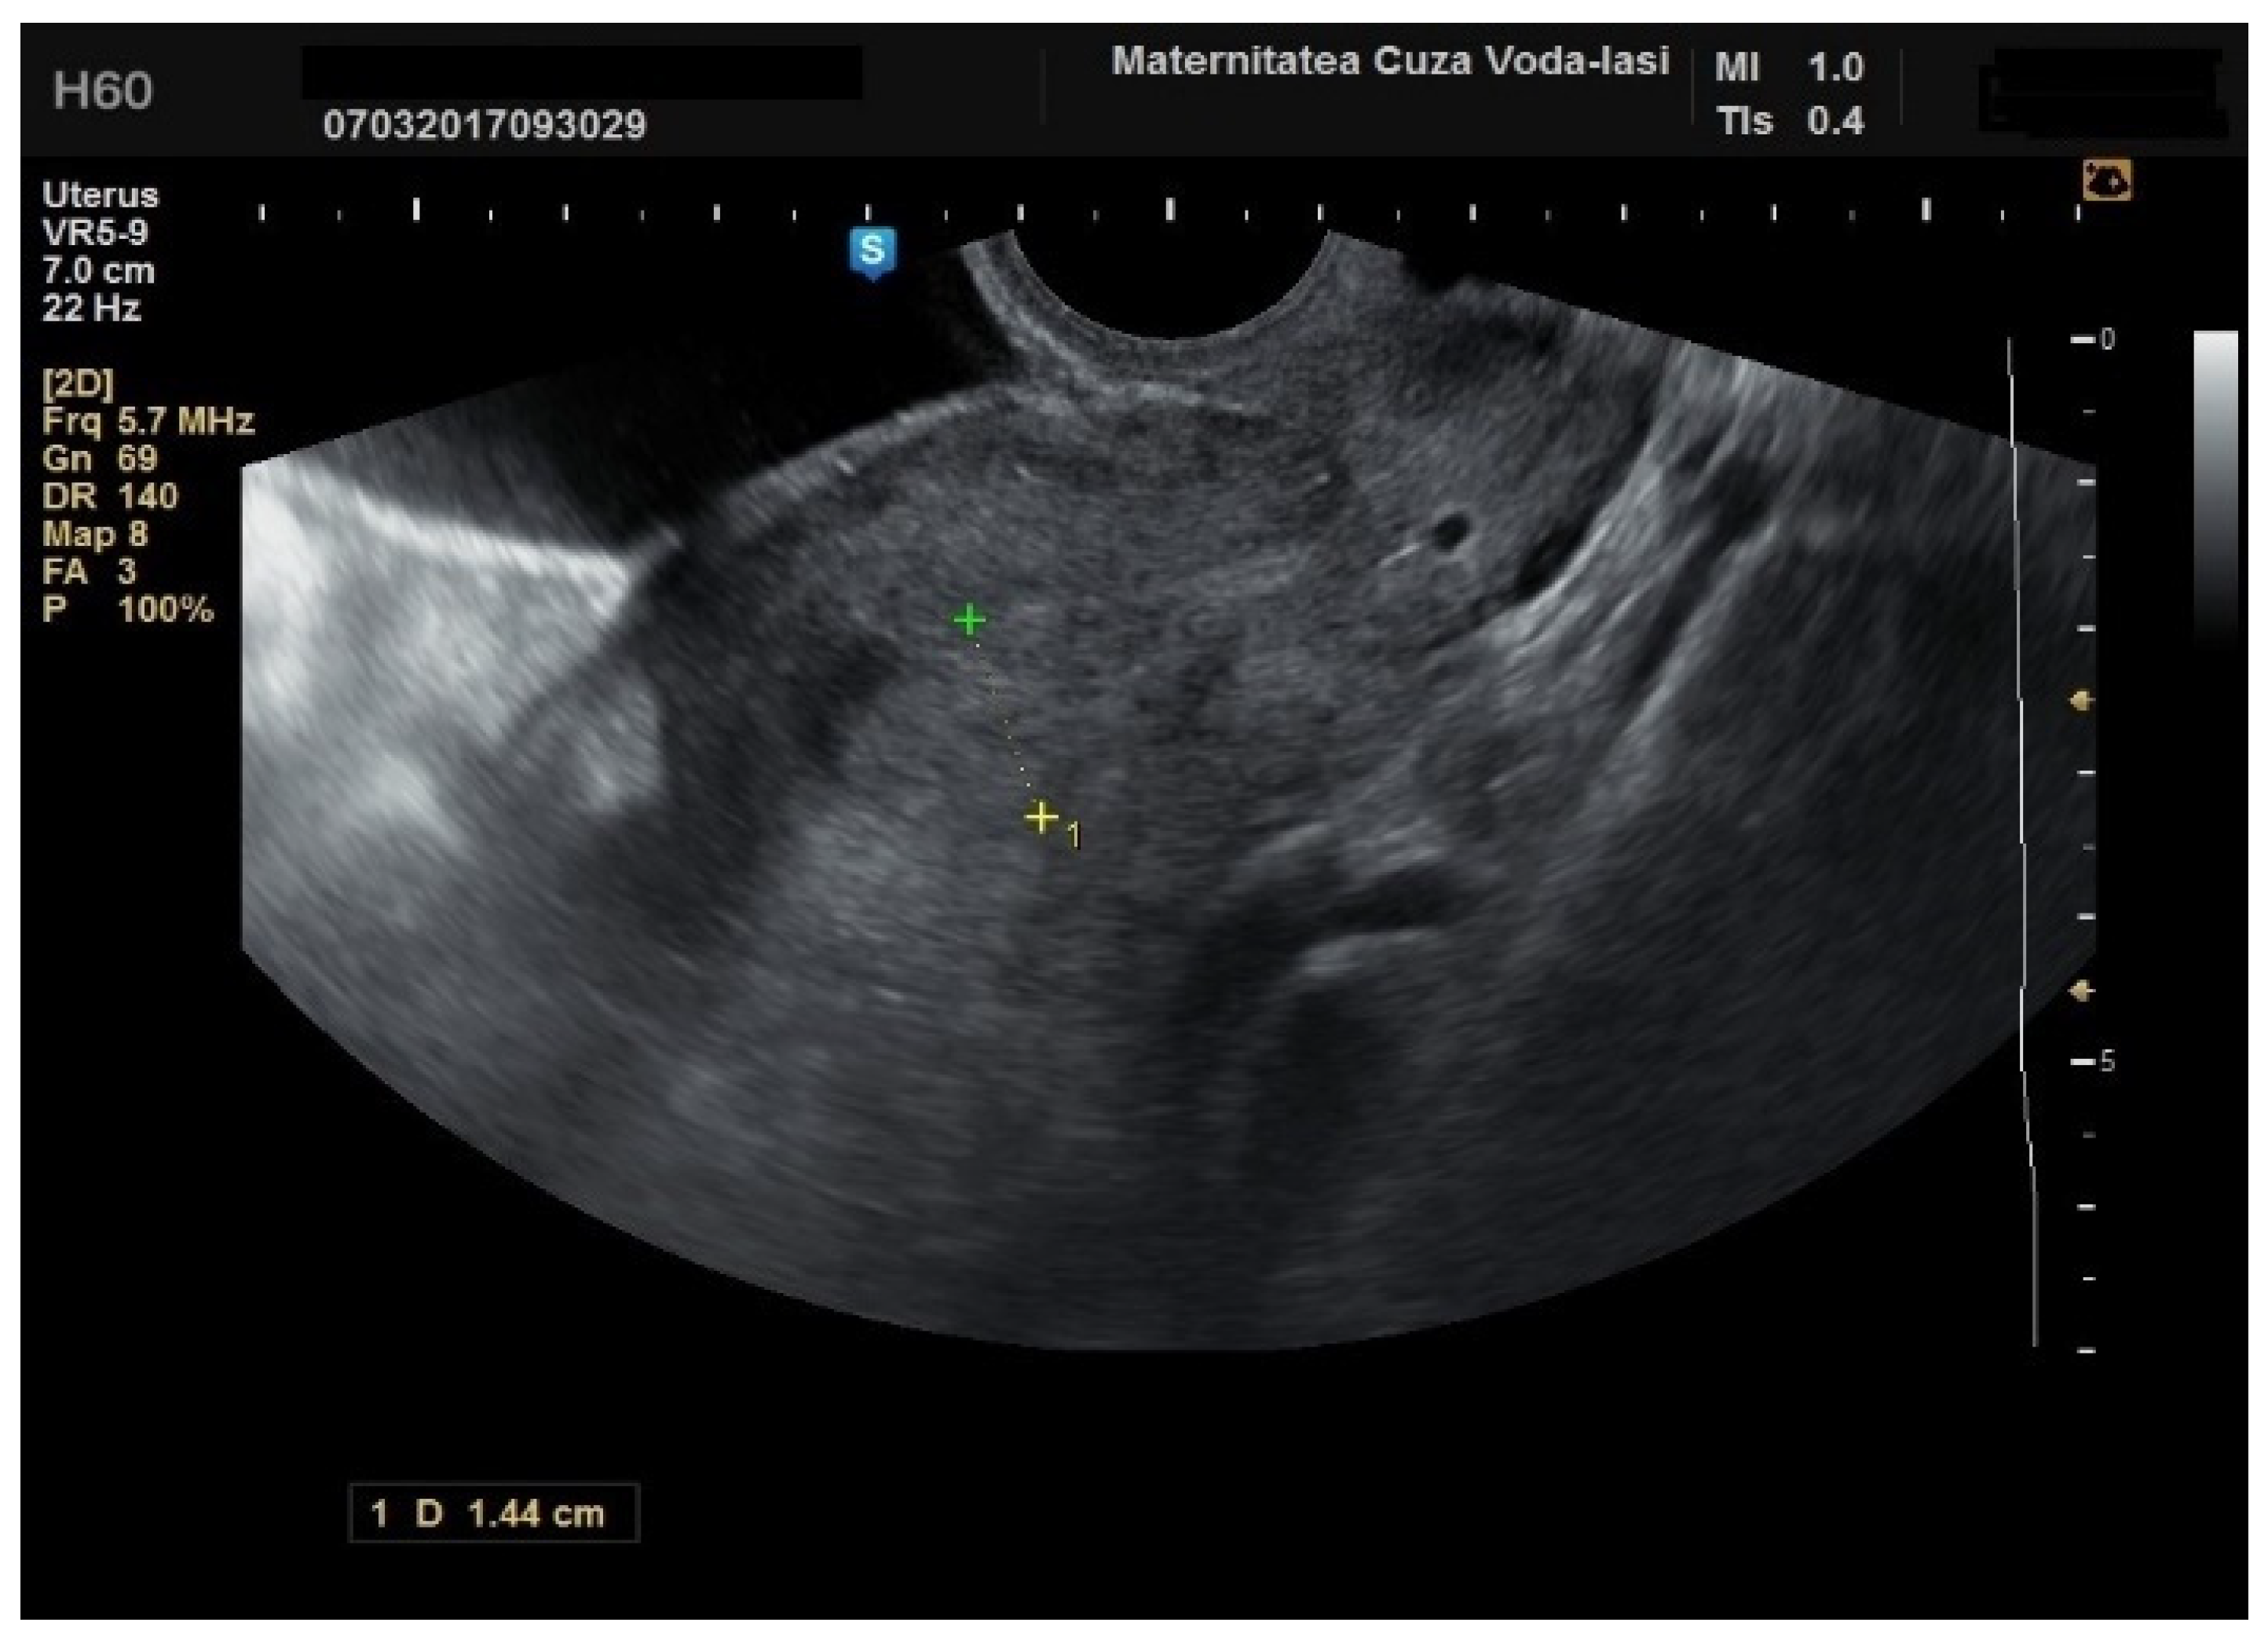

We accurately assessed the depth of myometrial invasion, greater or less than 50%, for all patients with endometrial malignancy (Figure 13 and Figure 14) using a subjective method. Furthermore, the depth of myometrial invasion was also verified preoperatively with magnetic resonance imaging (MRI). In each case of endometrial malignancy, our pathology department appreciated the invasion by conducting a frozen section during surgery, as well as through the final paraffin-based histopathological exam.

Figure 13. Ultrasound imaging in endometrial cancer: invasion of the posterior myometrium extending less than 50%—without vascularization.